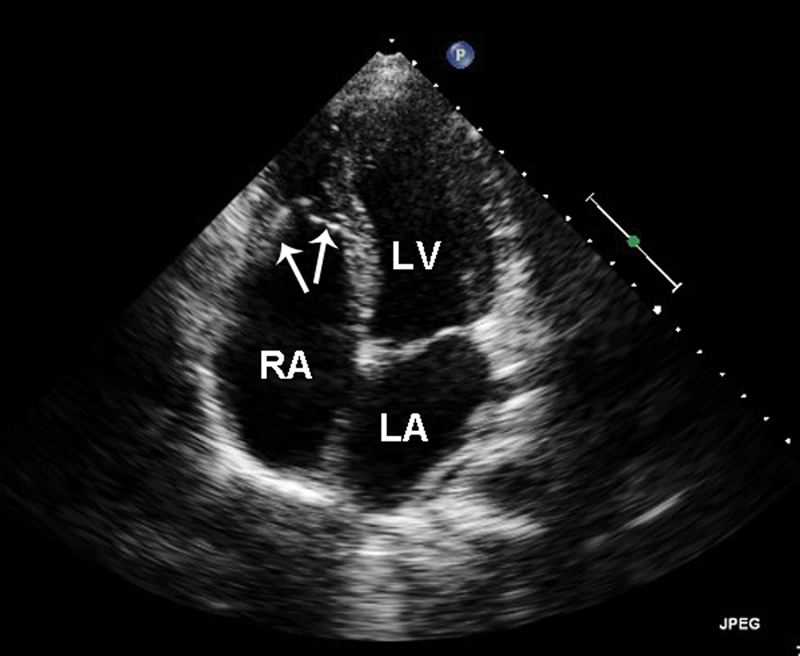

فحوصات تشخيصية لبعض امراض القلب والشرايين التاجية